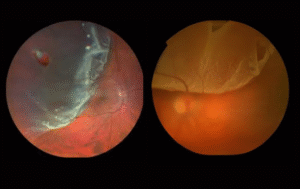

There are two types — Dry ARMD and Wet ARMD. The dry form develops slowly, while the wet form progresses rapidly due to abnormal blood vessel growth under the retina.

While ARMD has no complete cure, early diagnosis and treatment can significantly slow its progression. Advanced options such as anti-VEGF injections, laser therapy, and nutritional supplementation help maintain functional vision.